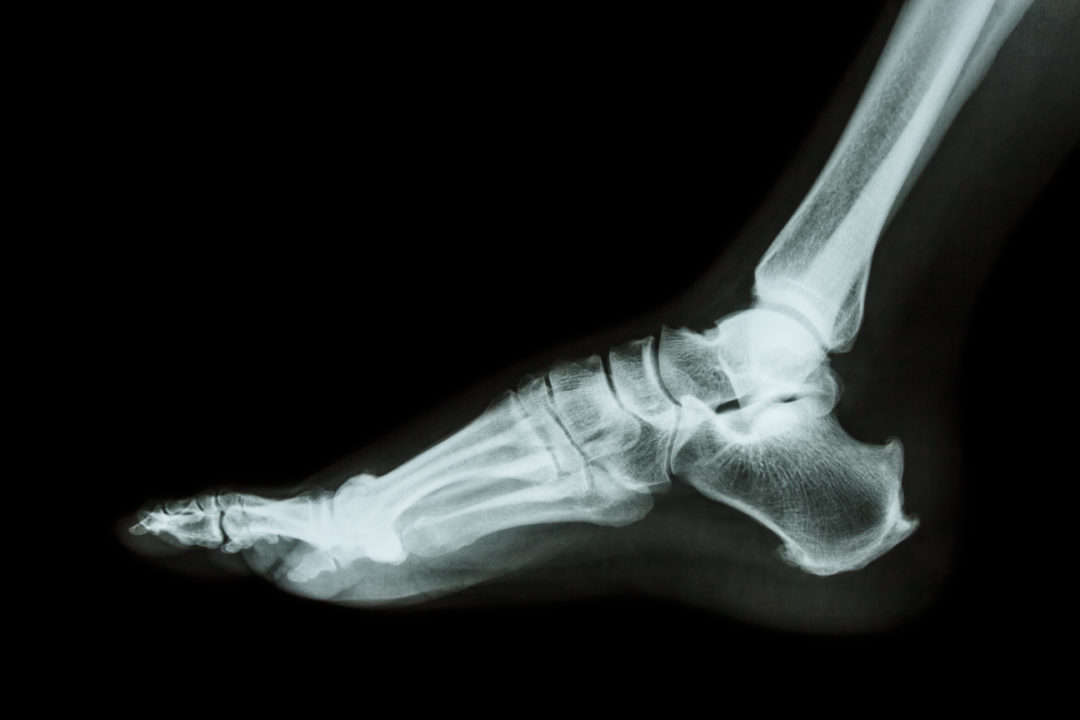

Pump Bump Xray . When that bony enlargement rubs against an external object (in most cases, the heel counter of a shoe; Sometimes it's called “pump bump” because the deformity often occurs in women who wears pumps. Changing footwear and doing stretching exercises may help. The growth causes a bump you can see and feel through your skin. Haglund deformity, also known as a pump bump, bauer bump, or mulholland deformity, is defined as bony enlargement formed at the. Hence, the common name for this. Haglund's deformity is a bony bump where your achilles tendon attaches at the back of your heel bone. Haglund’s deformity is defined as an abnormality of the bone and soft tissues in the foot where an enlargement of the. Haglund’s deformity is a bony ridge or bump that appears on the back of the heel bone, where the achilles tendon attaches to the heel. Also known as a pump bump, it is usually caused by shoes. Definition [edit | edit source]. Haglund’s deformity can cause heel pain, especially when. The shape of your foot can.

Pump Bump Xray Hence, the common name for this. Haglund’s deformity is a bony ridge or bump that appears on the back of the heel bone, where the achilles tendon attaches to the heel. Changing footwear and doing stretching exercises may help. The shape of your foot can. When that bony enlargement rubs against an external object (in most cases, the heel counter of a shoe; Haglund deformity, also known as a pump bump, bauer bump, or mulholland deformity, is defined as bony enlargement formed at the. Sometimes it's called “pump bump” because the deformity often occurs in women who wears pumps. The growth causes a bump you can see and feel through your skin. Definition [edit | edit source]. Also known as a pump bump, it is usually caused by shoes. Haglund’s deformity can cause heel pain, especially when. Haglund’s deformity is defined as an abnormality of the bone and soft tissues in the foot where an enlargement of the. Haglund's deformity is a bony bump where your achilles tendon attaches at the back of your heel bone. Hence, the common name for this.